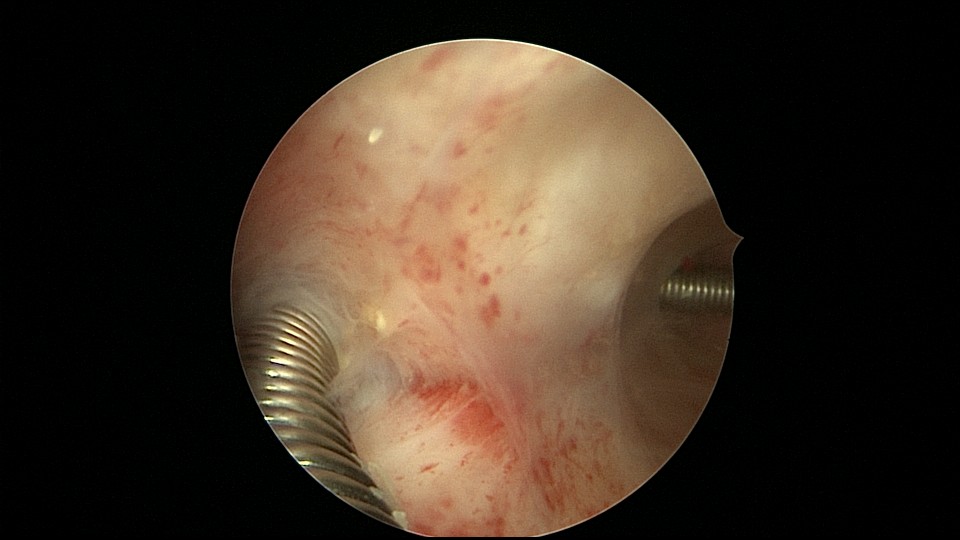

患者68岁,G3P1,顺产1次,安环42年,绝经20年,外院取环失败。子宫后位,宫颈及子宫萎缩,距宫颈内口1cm以上宫颈管封闭致密粘连,B超监护下异物钳分离粘连,打开进入宫腔的通道,艰难扩宫至6号扩宫棒,见O型环与两侧宫壁崁顿,异物钳无法取出,取环钩将环拉至宫颈外口,中弯钳牵拉,完整取出节育环,环变形,很艰难的取环经历。